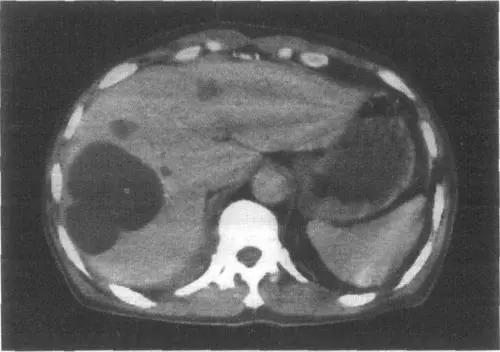

多発性肝嚢胞は多発性嚢胞性肝とも呼ばれ、多発性嚢胞性腎を有する患者に多くみられる。 多発性嚢胞性腎を有する患者では、肝嚢胞の発生率は加齢とともに増加するが、これは肝臓の内部構造の発達に関係している。

これらの多発性嚢胞腎患者のうち、30歳未満の患者では、多発性嚢胞肝臓を発症する確率は10〜20%である;一方、60歳以上の患者では、50~70%の確率で多嚢胞性肝臓を発症する。

合併症の危険性:多発性肝嚢胞患者は多発性嚢胞腎を伴うことが多く、統計によると、患者の約1/3~1/2が多発性嚢胞腎を伴っており、多発性嚢胞腎は腎不全につながる可能性があり、致命的な危険性がある。